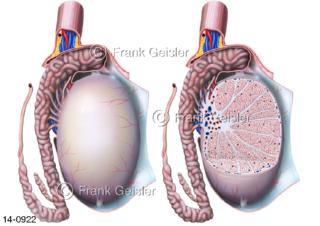

Bildergalerie Urogenitalsystem

Bilder zum Urogenitalsystem mit Urogenitalorgane, Urogenitaltrakt, zum Harn- und Geschlechtsapparat, Harnorgane und Geschlechtsorgane, Organe der Harnwege und der Fortpflanzung, Harnorgane und Geschlechtsorgane im männlichen und weiblichen Urogenitalsystem